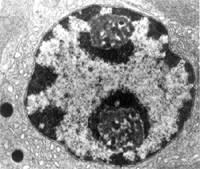

白細胞通過炎症的充血與滲出,使組織獲得更多的營養和抗體等。可中和毒素,消滅致炎因子,清除異物和組織碎屑。炎症的增生有助於組織的修復。同時全身反應的發熱可以促使機體代謝增強、血中白細胞增多、單核細胞吞噬功能加強、抗體生成增多等。

炎症對機體的損傷的局部組織所呈現的反應稱為炎症。根據持續時間不同分為急性和慢性。急性炎症以發紅、腫脹、疼痛等為主要徵候,即以血管系統的反應為主所構成的炎症。局部血管擴張,血液緩慢,血漿及中性白細胞等血液成分滲出到組織內,滲出主要是以靜脈為中心,但象蛋白質等高分子物質的滲出僅僅用血管內外的壓差和膠體滲透壓的壓差是不能予以說明的,這裡能夠增強血管透性的種種物質的作用受到重視。

疾病早期,因病理的可逆性,肉眼觀解剖學上很少器質性改變。隨疾病發展病理學變化逐漸明顯,肉眼可見肺過度充氣及肺氣腫,肺柔軟疏鬆,可合併有肺大泡。支氣管及細支氣管內含有粘稠痰液及粘液栓。支氣管壁增厚、黏膜腫脹充血形成皺襞,粘液栓塞局部可發現肺不張。顯微鏡下的改變比較明顯。即使在輕症的哮喘患者,可見氣道上皮下有肥大細胞、肺泡巨噬細胞、嗜酸性粒細胞、淋巴細胞與嗜中性粒細胞浸潤。哮喘發作期,氣道黏膜下組織水腫,微血管通透性增加,支氣管內分泌物貯留,支氣道平滑肌痙攣,纖毛上皮剝離,基底膜露出,杯狀細胞增殖及支氣管分泌物增加等病理改變。若哮喘長期反覆發作,表現為支氣管平滑肌的肌層肥厚,氣道上皮細胞下的纖維化等致氣道重構和周圍肺組織對氣道的支持作用消失。儘管哮喘的病因及發病機理均未完全闡明,但目前的治療方法,只要能夠規範地長期治療,絕大多數患者能夠使哮喘症狀能得到理想的控制,減少復發乃至不發作,與正常人一樣生活、工作和學習。為使哮喘診斷治療工作規範化,1994年在美國國立衛生院心肺血液研究所與世界衛生組織的共同努力下,共有17個國家的301多位專家組成小組,制定了關於哮喘管理和預防的全球策略(GINA)。中華醫學會呼吸分會也於1993年和1997年議定和修訂了中國的哮喘防治指南,促進了防治水平的提高。